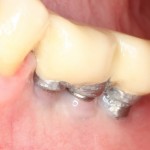

Нижние, вроде как, вполне держатся, на них стоят постоянные металлокерамические коронки. Помните, что я говорил про один из главных критериев качественной имплантологической работы? Состояние десны вокруг имплантов!

Хотите на это посмотреть? Этого не покажут, рекламируя базальную имплантацию:

То есть, друзья, десны нет. За подобную работу в наших клиниках рвут диплом в клочья и выгоняют нафиг. Для базальной имплантации, такая ситуация — норма:

И теперь представьте, как за всем этим ухаживать? Как этим жевать, если учесть тот факт, что ножка импланта, торчащая из десны, легко гнется? И сколько такие импланты вообще прослужат, если учесть сложную гигиену и неудобную форму протеза в этом участке?

Жаль, но мы вынуждены эти базальные импланты удалить, проводить остеопластику и ставить другие, обычные винтовые импланты. И, к счастью, уже закончили эту работу, как нибудь расскажу вам о ней.